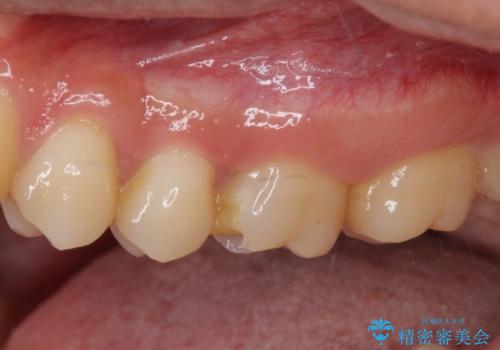

- 食事中にしばしば痛みを感じるとのことで来院された患者様です。

診査をしたところ、レントゲン写真よりとても大きなむし歯があることが分かりました。

虫歯が歯髄腔(神経の部屋)に達している可能性が非常に高かったため、炎症を起こしている神経組織を部分的に切除し、歯根部分の神経組織を保存する治療法が望ましいと考えられました。

処置開始前から神経組織を部分的に除去する可能性が高いことが分かっていたため、ラバーダムなどの環境を整え、無菌的環境下にて処置を進めて行きました。

虫歯は深くまで進行しており、歯冠部の神経から出血が認められました。神経を部分的に除去したところ出血が治まったので、生体親和性の非常に高いセメントにて充填し、仮封をしました。